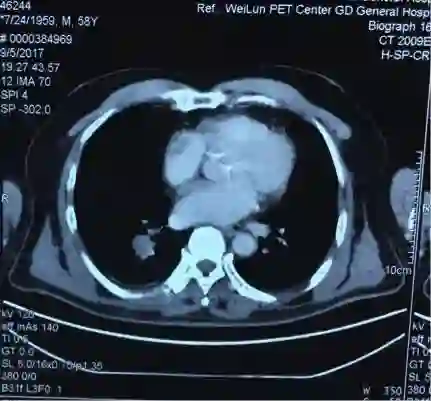

5. 2017-9-5广东省人民医院PET提示:右肺下叶肿物2.8*2.7cm,SUV 22.3,双侧颈部、双侧气管旁、隆突下、食管旁、右侧肺门淋巴结肿大,代谢升高,考虑为转移灶,右侧肾上腺转移灶,具体结果见下图:

(准备行经皮肺穿刺活检时图像)

吴一龙医生这个病例的PET-CT有一个特点,右肺下叶的病灶并不大,2.7*2.8cm,但是代谢非常高,高达22.3。这种小病灶高代谢的病灶,在肺癌患者中比较少见。尤其是代谢值大于20但病灶小的情况很少见。我同意谢主任刚的意见,如果该患者没有肾上腺的病灶,我认为诊断可以到此为止。我们可以看到,肺内的病灶有可能是肺内的淋巴结,我们已经对最大的淋巴结进行了活检,为良性病灶。但是,由于该患者多了肾上腺的病灶,用刚才的说法无法解释,肾上腺不属于淋巴系统。结合既往我们遇到的病例,我们现在有两个办法,我认为对于该患者,观察是一个办法,但是如果漏诊会比较麻烦,如果观察一段时间,下次过来复查提示病灶稍增大,我们如何处理?因此我认为现在我们要明确诊断,需要取病理活检,但是是取肺部病灶还是肾上腺的病灶?